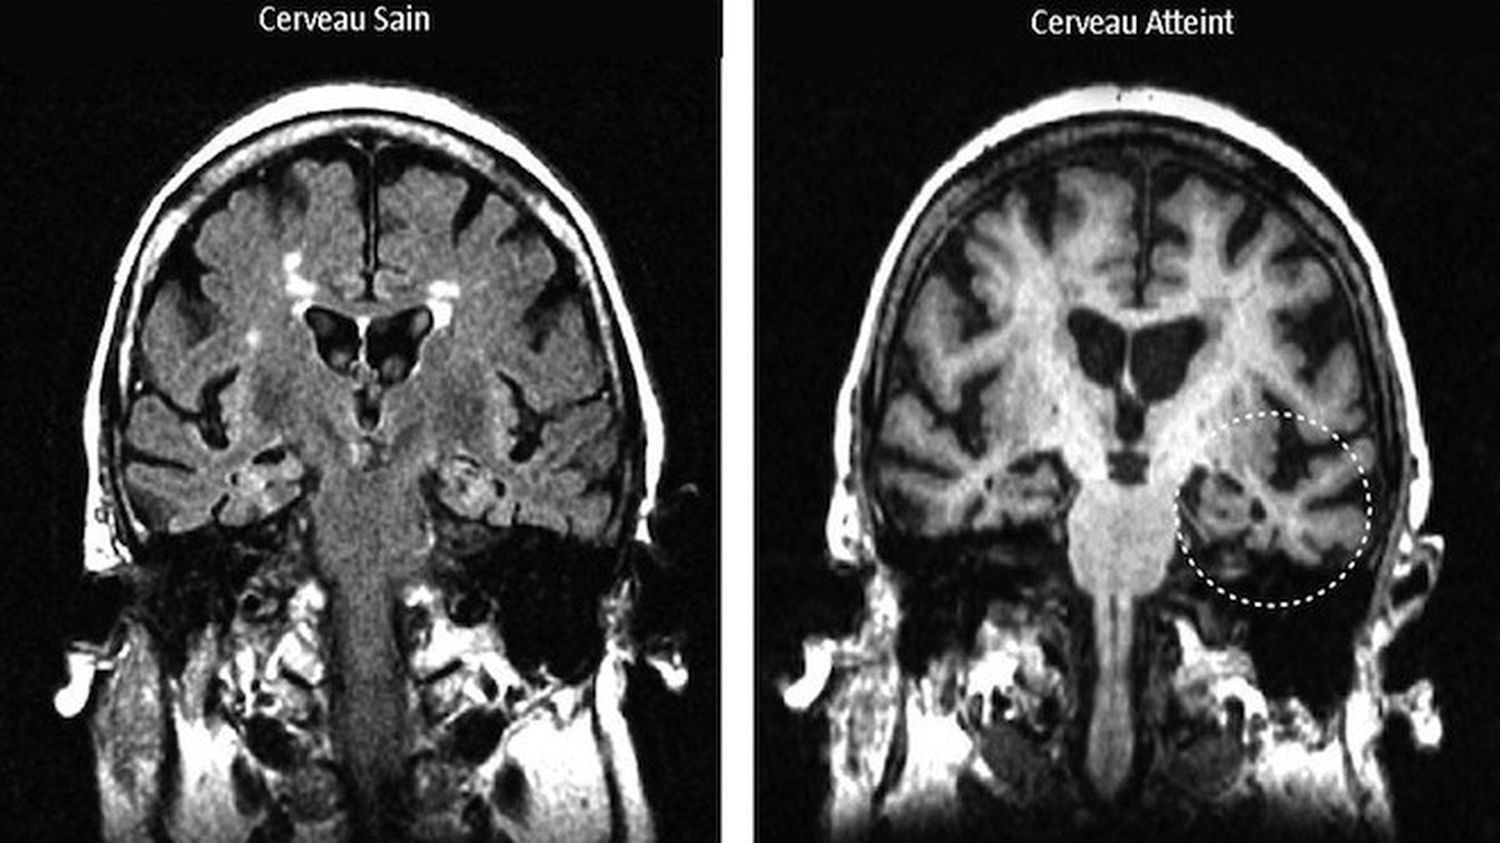

Dans des modèles murins d’Alzheimer, les scientifiques ont détecté des niveaux élevés de TSPO chez des souris âgées de six semaines seulement — un âge équivalent à 18 ou 20 ans chez l’être humain. Cette hausse a été observée dans le subiculum, une région essentielle à la mémoire. Ce signal précoce laisse penser que l’inflammation cérébrale intervient dès les premières étapes de la maladie, bien avant la dégradation cognitive.

Le pic de cette protéine coïncide avec la formation de plaques amyloïdes, ces amas de protéines qui s’accumulent dans le cerveau et perturbent la communication neuronale. Les chercheurs ont constaté que les cellules immunitaires appelées microglies étaient à l’origine de la majorité de ce signal. Ces cellules, censées éliminer les plaques, finissent par déclencher une inflammation chronique au lieu de protéger le cerveau.